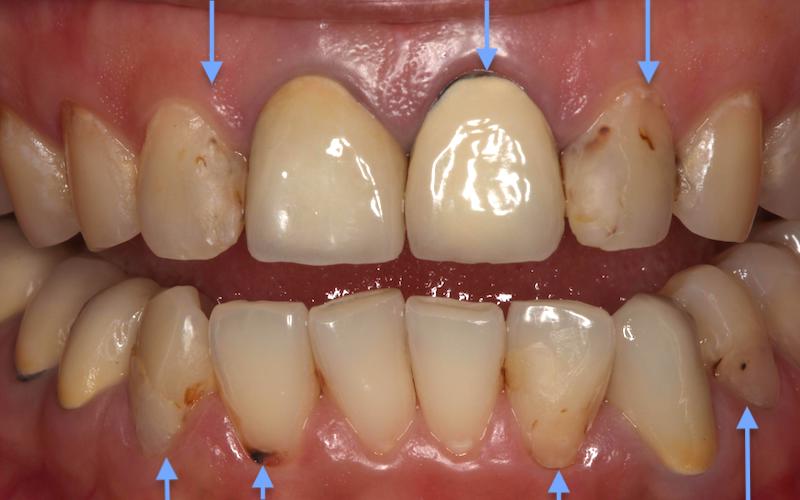

除了很多蛀牙,牙齦萎縮造成牙根外露,可能都是造成牙齒敏感酸痛的原因。除了診斷齲齒蛀牙以外,也使用牙周探針配合X光片,特別檢查患者的牙周狀況是否有潛在風險。診斷結果是全口輕微牙周炎,因此改善牙齒酸痛敏感症狀,也施以定期半年牙結石清除並且改善口腔衛教,患者順利地完成牙周維護。

五年後,患者的兩邊側門牙蛀牙範圍變大,右側門牙根部底端有發炎與齒槽骨破壞的情況,因為蛀牙蛀到神經,神經發炎壞死後感染蔓延到根尖所導致。上面四顆門牙經根管治療後,葉立維採用全瓷冠修復,患者對治療的結果非常滿意,半年後又在兩邊的犬齒和第一小臼齒也裝了陶瓷貼片,使得顏色更加一致。

若是使用複合樹脂或是傳統假牙來修復齲齒,由於樹脂不論是強度、顏色穩定性或是邊緣密合度都欠佳,多年後會明顯看到脫落、邊緣變色或是二次蛀牙的情況。這也是患者下定決心要做全面改善,改用全瓷牙冠與陶瓷貼片,接受更高品質的醫療的原因。而這過程中,使用的是當代牙醫診所最新的DSD數位微笑設計幫她進行整個療程。